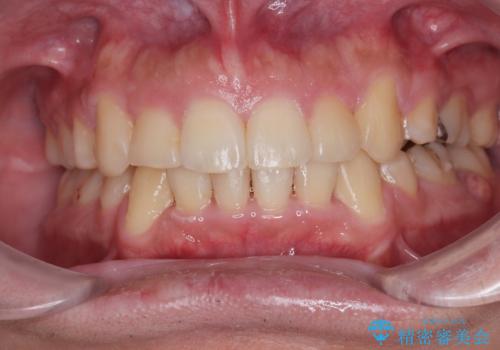

- 以前の矯正治療の後戻りにより、上の前歯にスペースができたことを気にして来院された患者様です。

インビザラインを用いて前歯のスペースを閉じつつ、上下の咬み合わせを構築していくこととしました。

隙間の空いてしまった前歯は、矯正治療で治療を行っても後戻りが起こりやすい傾向にあります。

マウスピースの保定装置をしっかりと装着しても空いてしまうため、細いワイヤーによる保定を併用することで後戻りを防止しています。